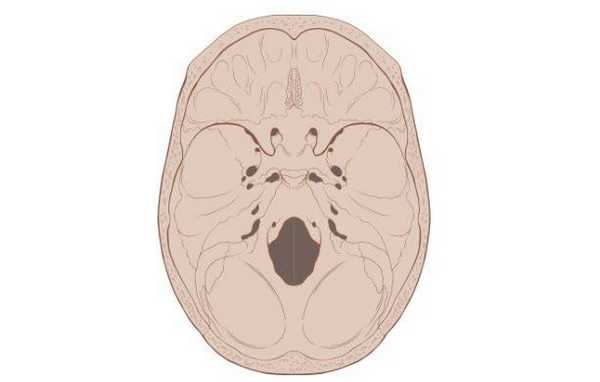

Схематическое изображение основания черепа

Основание черепа - область, образуемая затылочной, височными, решетчатой, лобной и клиновидной костями. Внутренняя поверхность данной анатомической структуры играет роль площадки, на которой покоится головной мозг. Через большое отверстие затылочной кости проходит ствол мозга. Наружная поверхность основания черепа богата нервными волокнами, кровеносными сосудами, связками и сухожилиями.

Основание черепа: вид изнутри и снизу

Из-за данных анатомических особенностей любая патология, возникающая в этой области, как правило, приводит к тяжелым последствиям. В подобных условиях для диагностики с успехом используется компьютерная томография основания черепа. Более того, КТ основания черепа может быть более информативным и специфичным методом обследования, по сравнению с магнитно-резонансной томографией.